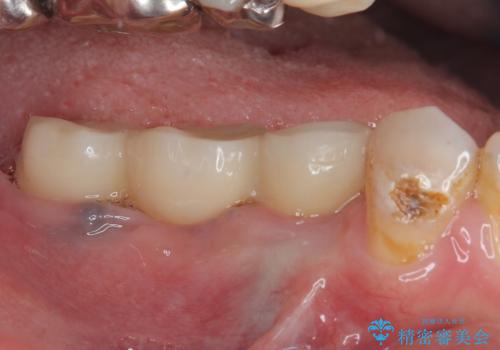

インプラントは、根管治療をした歯と比べると、破折するリスクは圧倒的に低いですが、こちらの方のように、臼歯しか咬合していない場合、歯ぎしりによる負担でインプラント周辺の骨が吸収する可能性があります。

就寝時のマウスピースの装着と定期的な通院によるレントゲン撮影や咬み合わせのチェックが必須となります。